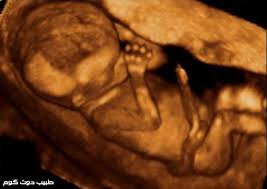

تطور الجنين في الشهر الثالث من الحمل الأسابيع 9 10 11 12 طبيب دوت كوم

مراحل تطور الجنين بالصور والفيديو في الاسابيع والشهور والقرأن الكريم الاحلام بوست